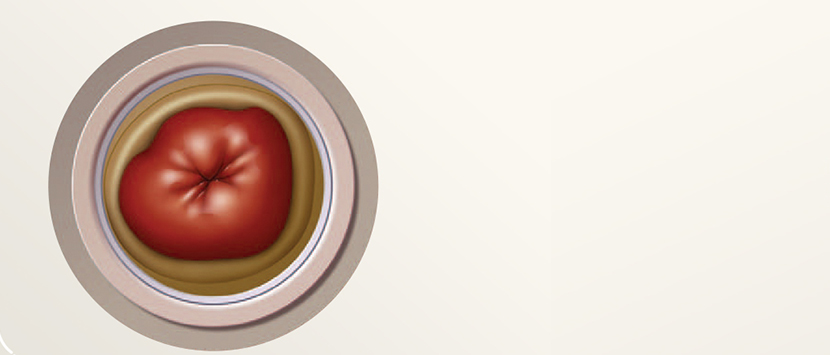

장루는 크기가 다양하며 모양이 둥글거나 타원형이거나 불규칙할 수 있습니다. 피부에 닿아 튀어나오거나 평평하게 유지될 수 있습니다.

장루에는 몇 가지 유사점이 있습니다. 모든 장루는 입 안과 비슷하게 광택이 나고 축축하며 붉은색이어야 합니다. 장(요)루에는 신경 말단이 없습니다. 따라서 아프지 않아야 합니다. 그러나 혈관이 풍부하여 자극을 받거나 문지르면 약간의 출혈이 있을 수 있습니다. 이는 정상이지만 출혈이 지속되거나 장(요)루에서 분비물이 섞여 나오면 의료 전문가와 상의하십시오. 1